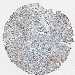

Average pTPM 3.7

Number of samples 521